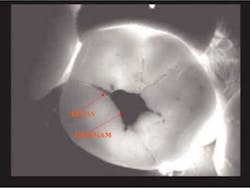

Early inter-proximal decay #12 (DIFOTI and X-ray)

Accurate diagnosis of occlusal caries is problematic at best. Prior to fluoride, the explorer could be retained in an occlusal fissure by factors other than decay. Brown in The Journal of Dental Education (1993) had concerns relative to the reliability and validity of making a diagnosis of occlusal decay based on the retention of an explorer in an occlusal fissure.

By the time there is radiographic evidence of decay, much of the occlusal enamel is undermined. Occlusal decay in patients who have used fluoride in the early years of life has a different anatomical model. The fissures are not open, thus do not give easy access to the dental explorer. The carious lesion starts at the base of the fissure and spreads within the tooth. DIFOTI is particularly efficient in diagnosing this type of decay.

Many may say the above DIFOTI image (Fig. 2) only demonstrates stained fissures. The explorer would not enter the fissures at all. The DIFOTI diagnosis was confirmed with a Diagnodent reading in excess of 70. The tooth was restored in a minimally invasive fashion.